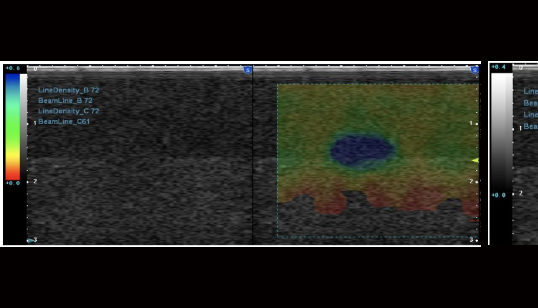

弹性成像

Elasticity imaging: 弹性成像

Freehand elasticity imaging: 徒手弹性成像(FEI)

基于应力的弹性应变成像,提供组织软、硬病变的诊断信息

• 徒手弹性成像是通过移动探头对检测部位进行挤压使组织产生运动,并利用回 波信号进行运动检测得到表征组织弹性的应变图像

Acoustic Radiation Force Imaging: 声辐射力弹性成像(ARFI)

基于声能 (ARFI)和剪切波波速的实时弹性成像,提供组织软、硬病变的定量评价。 通过自动发射一定能量的声波通过声辐射力直接对所需要检测部位进行激励,用 于激励的声波犹如无形的手直接去推动组织产生运动,从而得到表征组织弹性的图像,这种新兴弹性成像技术可以得到更精确的组织应变图像

shear wave imaging:剪切波成像技术(SWI)

基于ARFI技术衍生的超声剪切波成像,通过调整脉冲激励方式,根据水平方向多个点的位移-时间曲线估算横向传播的剪切波波速,然后利用剪切波传播特性与生物组织弹性特征之间的内在联系,最终定量重构组织的弹性模量以形成二维的图像。